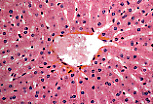

肝小叶的组成成分

每个小叶由肝细胞组成的肝细胞索(雷马克索,travées de Remak)构成;肝细胞索围绕中央静脉(小叶中央静脉)呈放射状排列。

来自门静脉分支的血液在雷马克索之间的血窦中流动,血窦汇流至中央静脉,再由中央静脉将血液输送至肝静脉。

中央静脉接收流经肝实质血窦的血液。

因此,肝血窦构成了一个 独特的毛细血管网 ,连接于两条静脉之间。

雷马克索由单层上皮样肝细胞板构成,肝细胞板可局部吻合;

血窦占据肝细胞索之间的间隙。

肝细胞

肝细胞为多面体细胞,细胞核染色浅,含1-2个大核仁;细胞质呈颗粒状。 嗜碱性最强的区域对应粗面内质网聚集区,染色浅的区域则为糖原或脂质包涵体。

每个肝细胞有两个血管极(或血管面)朝向血窦,以及肝细胞间的接触面(称为胆小管极); 肝细胞通过质膜内陷形成胆小管,肝细胞产生的胆汁排入胆小管中。

肝细胞常可见双核,或细胞核体积大于平均水平(多倍体细胞)。 正常成年肝脏中核分裂象极少见,因为正常情况下肝细胞的更新速度极慢。